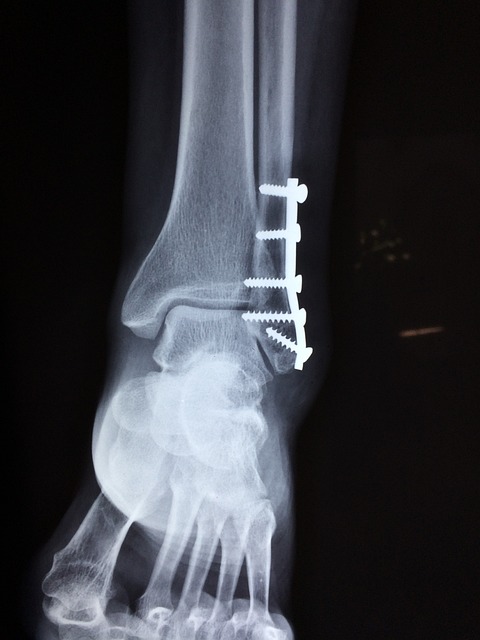

9.염좌

발을 다쳐 통증이 생기게 되는 경우로, 인대가 찢어지거나 늘어나 관절이 제자리 위치가 아닌 상태에서 강제로 움직이게 되면 통증이 나타나게 됩니다. 특히나 운동선수들이 발목 관절을 무리하게 움직이는 편으로, 발 염좌가 흔하게 생길 수 있습니다. 염좌가 생긴다면 불편한 증상과 함께 발이 부어오르게 됩니다. 또한 증상이 심각해지면 피부색 변화도 초래하게

됩니다.